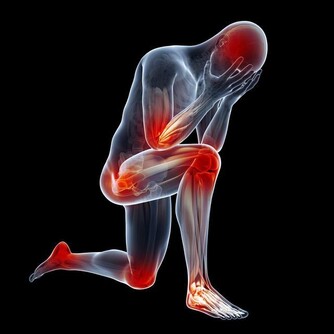

1、我們四肢主要是受大腦皮層的控制,當進入睡眠狀態時,大腦皮層就會抑制四肢肌肉的活動,但是這個時候肌肉神經會有一些自發的運動,加上睡眠狀態時,人體內的血液循環較慢,小小的肌肉神經運動會表現得更加明顯。

2、睡覺狀態下忽然的抖動是神經系統發現你忽然陷入睡眠,很久沒有活動,它以為你死了,所以它就動動想試試你死了沒有…開懷一下,總之睡覺時身體突然抖一下屬於正常現象。~